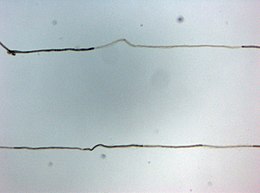

La caractéristique pathologique de la maladie est la perte de la gaine de myéline (l'enveloppe graisseuse qui isole et protège les fibres nerveuses) des nerfs périphériques. Un dysfonctionnement du système immunitaire, qui protège normalement le corps contre les agressions externes, produit des anticorps ou des globules blancs (lymphocytes) anormalement dirigés contre la gaine de myéline, entraînant alors un défaut de transmission des informations et ainsi les symptômes de la maladie.

- l'électromyogramme montre typiquement une diminution de la vitesse de propagation de l’influx électrique sur les nerfs, mais ces anomalies peuvent manquer. Dans ce cas, d’autres examens sont alors nécessaires pour conforter le diagnostic ;